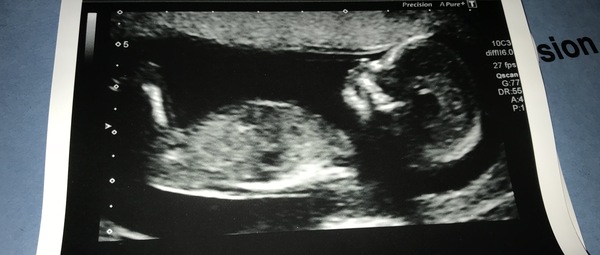

Hi all, I posted in the first thread but have been catching up with everyone’s news today. I am now 13.4 weeks EDD, Sept 6th and had my booking in scan this morning, a week late due to the snow. I have had hyperemesis since week 5 and thought I was getting over the worst of it but from Friday it has completely ramped up again, probably due to another kidney infection. I’m now a bit worried to be taking more antibiotics along with regular anti sickness (which again doesn’t seem to work) anyone else been bothered with Kidney or urinary tract problems? Have attached a photo of the little trouble maker.

Love the scan pics!

Beautiful scans Hannah and Mummy